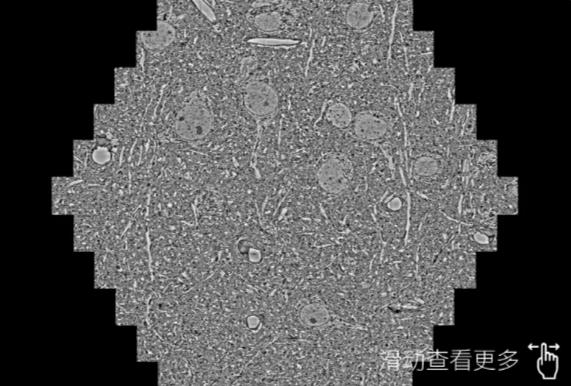

鼠脑切片。左图使用林芝蔡司林芝扫描电镜MultiSEM706对165μmx143pm面积区域成像,耗时仅需1.5秒。右图为鼠脑切片中30μm区域放大效果。样品由芝加哥大学B.Kasthuri提供。

使用蔡司高速林芝扫描电镜MultiSEM对1mm²人脑皮层组织进行高分辨成像,并对其中的各种细胞结构进行三维重构分析。左图展示了2x3mm²组织平面中锥体神经元的三维重构效果。右图显示了局部体积神经元三维重构。图像由哈佛大学chtman实验室提供,渲染图由D. Berger 制作。